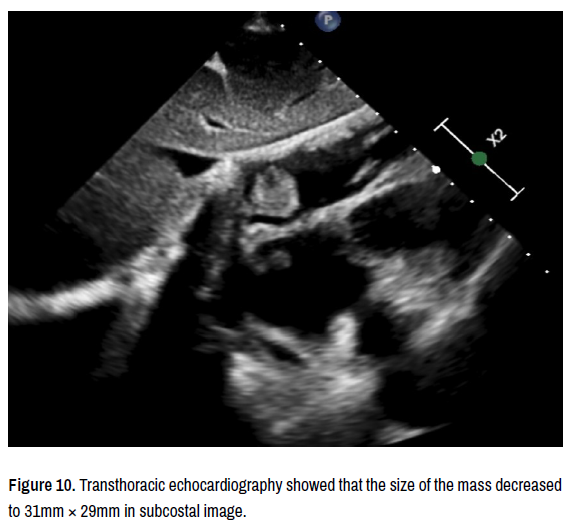

In the immunohistochemical and histopathological study, synaptophysin (+), pancytokeratin (+), chromogranin (+), TTF-1 (-). Ki-67 score was found to be 80-90%. The biopsy revealed small-cell lung carcinoma, and it was considered that primary focus was in the lung with direct invasion to the heart. As a result patient was diagnosed stage 4 lung carcinoma and consulted to oncology and referred to relevant department. The patient was started on combined radiotherapy and etoposide, cisplatin as a chemotherapy regimen. After 3 months of chemotherapy treatment, the patient underwent control PET-CT and transthoracic echocardiography in response to the treatment. The examinations showed that the tumor size decreased and the patient responded to the treatment. It was observed that the tumor size decreased. Transthoracic echocardiography showed that the size of the mass decreased to 31mm × 29mm. It was observed that FDG uptake decreased in control PETCT (Figures 9-12).

Figure 10. Transthoracic echocardiography showed that the size of the mass decreased to 31mm × 29mm in subcostal image.